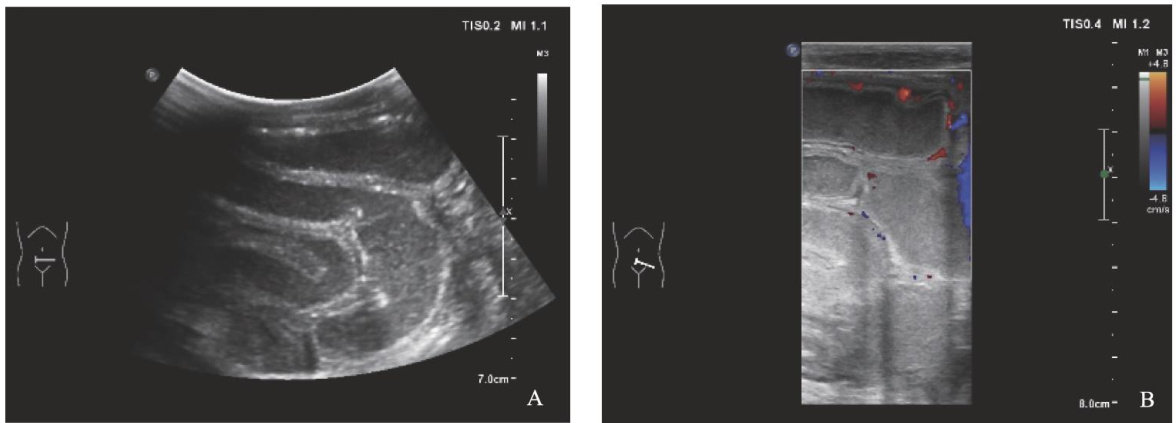

线粒体神经胃肠型脑肌病临床及肠道超声表现一例

ABSTRACT:Mitochondrial neurogastrointestinal encephalomyopathy(MNGIE),a rare mitochondrial disorder caused by TYMP gene mutations,is characterized by severe gastrointestinal dysmotility,peripheral neuropathy,and leukodystrophy.Thisarticlesummarizes the clinical data and intestinal ultrasound findings of a MNGIE case,aiming to provide insights for clinical diagnosis and treatment.

线粒体神经胃肠型脑肌病(mitochondrialneurogastrointestinalencephalomyopathy,MNGIE)是一种由TYMP基因突变导致的罕见常染色体隐性遗传病,以胃肠道动力障碍、周围神经病变及脑白质损害为特征[1-2],临床表现复杂多样,常因非特异性消化道症状(如慢性腹泻、假性肠梗阻)被误诊为克罗恩病或功能性胃肠病[3],导致延迟诊断及不必要的手术干预。(剩余5239字)